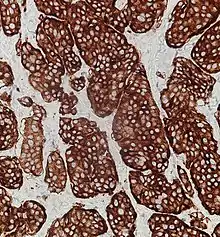

Synaptophysin immunohistochemistry of neuroendocrine tumor, staining positively

Given the diverse secretory activity of NETs there are many other potential markers, but a limited panel is usually sufficient for clinical purposes.[1] Aside from the hormones of secretory tumors, the most important markers are: